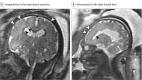

Results: Of the 82 women, 80 were from Colombia and 2 were from the United States. In 3 of 82 cases (4%), fetal MRI demonstrated abnormalities consistent with congenital ZIKV infection. Two cases had heterotopias and malformations in cortical development and 1 case had a parietal encephalocele, Chiari II malformation, and microcephaly. In 1 case, US results remained normal despite fetal abnormalities detected on MRI. Prolonged maternal polymerase chain reaction positivity was present in 1 case. Of the remaining 79 cases with normal results of prenatal imaging, postnatal brain MRI was acquired in 53 infants and demonstrated mild abnormalities in 7 (13%). Fifty-seven infants underwent postnatal cranial US, which detected changes of lenticulostriate vasculopathy, choroid plexus cysts, germinolytic/subependymal cysts, and/or calcification in 21 infants (37%).